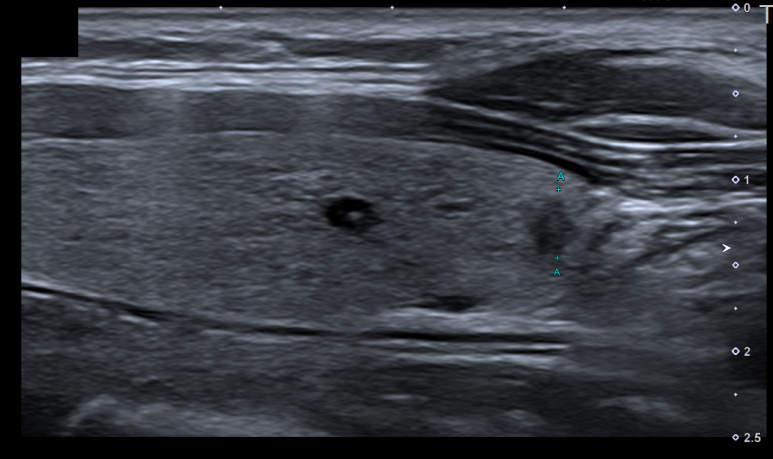

다음 영상은 얼마 전 저희 병원을 방문한 분의 갑상선 초음파 소견입니다. 환자는 1년 전부터 오른쪽 목에 이물감을 호소하고 원인을 확인하기 위해 내원했습니다.

갑상선 초음파

갑상선 초음파

갑상선 초음파 결과 좌갑상선 하부에서 크기가 약 4mm가 되는 아주 작은 결절이 발견되었으며 불규칙한 테두리와 폭보다 높이가 긴 형태(Tallerthanwide), 저 에코성(주변 갑상선 조직보다 어두운 소견)이 확인되어 갑상선암 혐의로 세침흡인검사(조직검사)를 시행하였습니다.세침흡입검사란 초음파를 보면서 주사기(혈액검사를 할 때 사용하는 일반적인 주사기)를 사용하여 결절 세포를 채취하는 것을 말합니다.

안타깝게도 조직검사 결과 갑상선 유두암(Papillary thyroid carcinoma)이 확인되어 치료하고자 본원에서 신속하게 조치를 취하여 대학병원에 진료의뢰하였습니다.